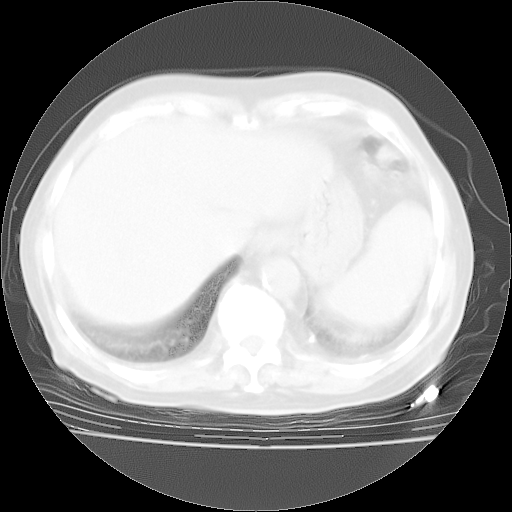

4月28日肺部CT——再次出现类似去年5月9日——透光度降低,“间质性”改变。

4月28日肺部CT——再次出现类似去年5月9日——磨玻璃样、间有“粟粒样”改变。

个人阅读4.14日肺部CT平扫:纵隔窗无异常,但肺窗示:双下肺内、后基底段有片絮状侵润影,部位以后基底段为著,以间质改变为主,呈急性肺泡炎征像,和首次住院影像学有相似之处。仅是个人读片,明日请相关专家再读片哈。其它建议同上。